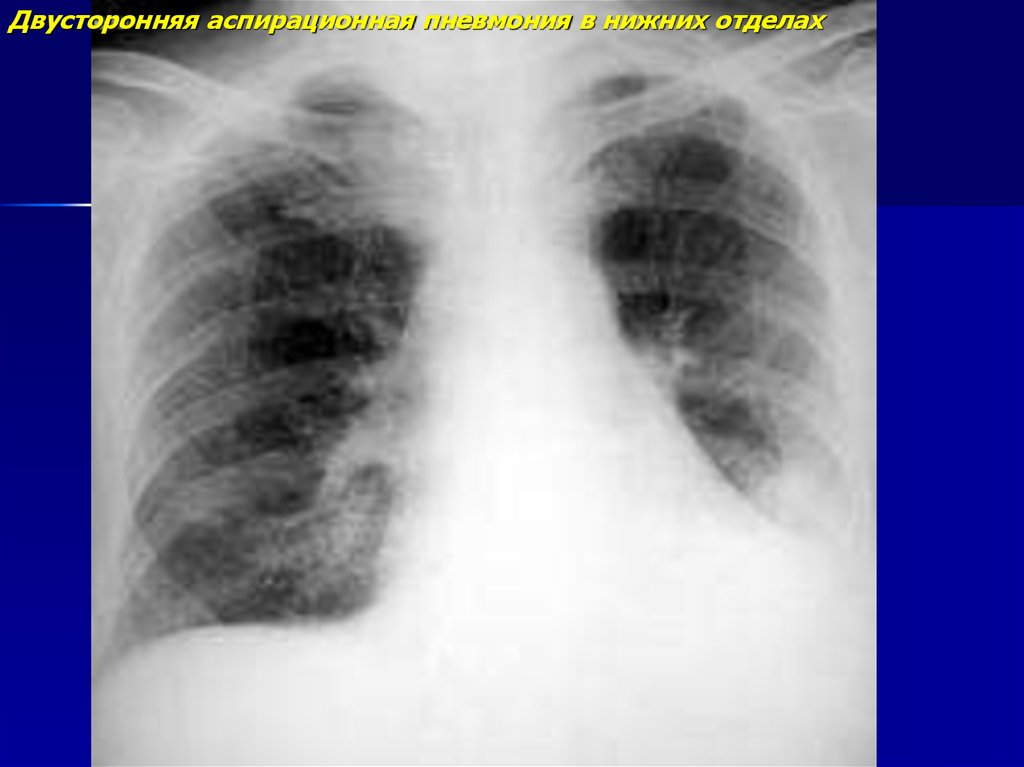

Двусторонняя аспирационная пневмония в нижних отделах